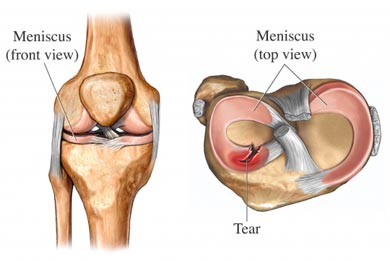

Розрив меніска є найчастішим і відносно нетяжким пошкодженням в коліні. Для його виникнення іноді буває досить навіть незначної травми, найчастіше при поєднанні згинання та обертання. Типові приклади - удар по м'ячу «щіточкою», вставання з положення присідання, різкий поворот при ходьбі або бігу.

Типовий розрив меніска з вивихом типу «ручка лійки» на схемі і через артроскоп

Ознаки розриву меніска – раптовий колючий біль в коліні при певному русі, що супроводжується відчуттям заскоку, клацання, блокування; раптова поява обмежень у згинанні або розгинанні коліна; набряк в коліні. Для підтвердження діагнозу проводиться магнітно-резонансна томографія.